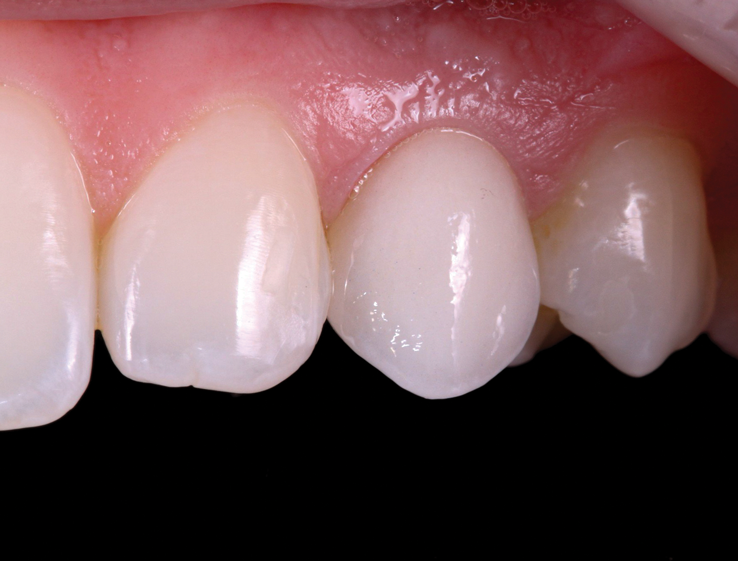

(44.) The provisional restoration was placed back on the implant and tightened to 15 Ncm while applying counter torque. Note that the papillae are partially supported without pressure and that the gingival embrasures are slightly open to allow incisal migration of the papillae during the integration and maturation phase.

Figure 44